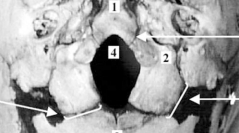

fr Fermeture des synchondroses intra-occipitales : implication dans la configuration du foramen magnum

Hélène COQUEUGNIOT & Jean-Marie LE MINOR

35-42, Publié le 31 janvier 2002, art. 1 (6) DOI